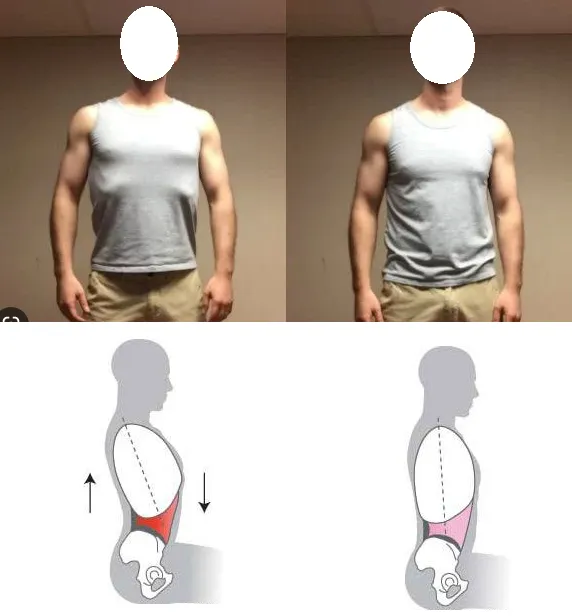

姿勢不良 -肌肉柔軟度不足、運動過度產生代償等等。

結構異常 -長短腳、扁平足、骨盆錯位、脊柱側彎、骨折、手術後等等。

腓腸肌位於小腿後方,而經常運動後不伸展或是長期不運動的習慣者皆屬於高風險族群。